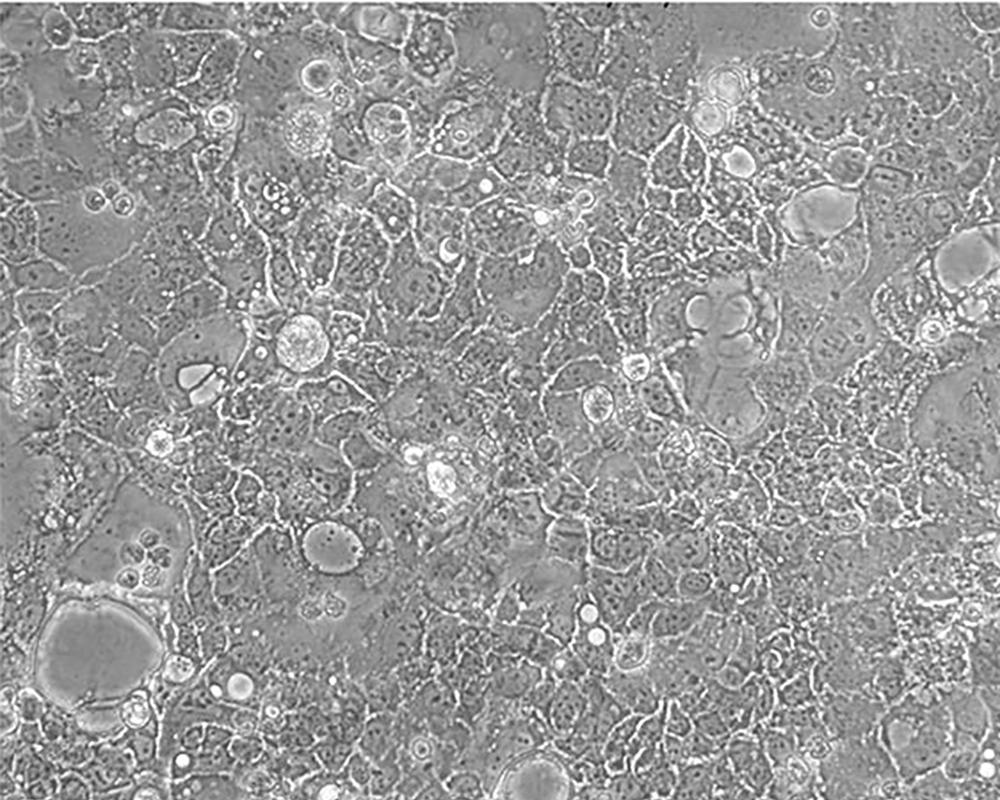

產品名稱 Caco-2

中文名稱 人結直腸腺癌細胞

生長特性 adherent

形態特征 epithelial

細胞描述 Upon reaching confluence, the cells express characteristics of enterocytic differentiation. Ref Caco-2 cells express retinoic acid binding protein I and retinol binding protein Ⅱ.